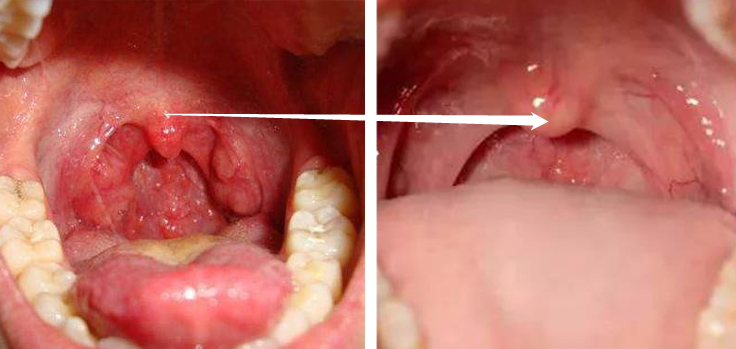

甲流和普通感冒相比,还是要严重不少的,传染力强、发烧概率高,特别是对咽喉、嗓子、呼吸道影响大!

很多人发烧好了、鼻涕不流了,但嗓子依然是刀片嗓!甚至咽喉痛、嗓子痛、咳嗽能持续好几个月!

喉咙疼+嗓子疼,双重加持,咽口水都疼,吃东西更是难受,就算喝特效药,也缓解不了。

所以,用上一段时间你会发现:原本受损的咽喉,现在不再有红肿感、吞咽不在有异物感、不再干燥、声音也不再嘶哑了。